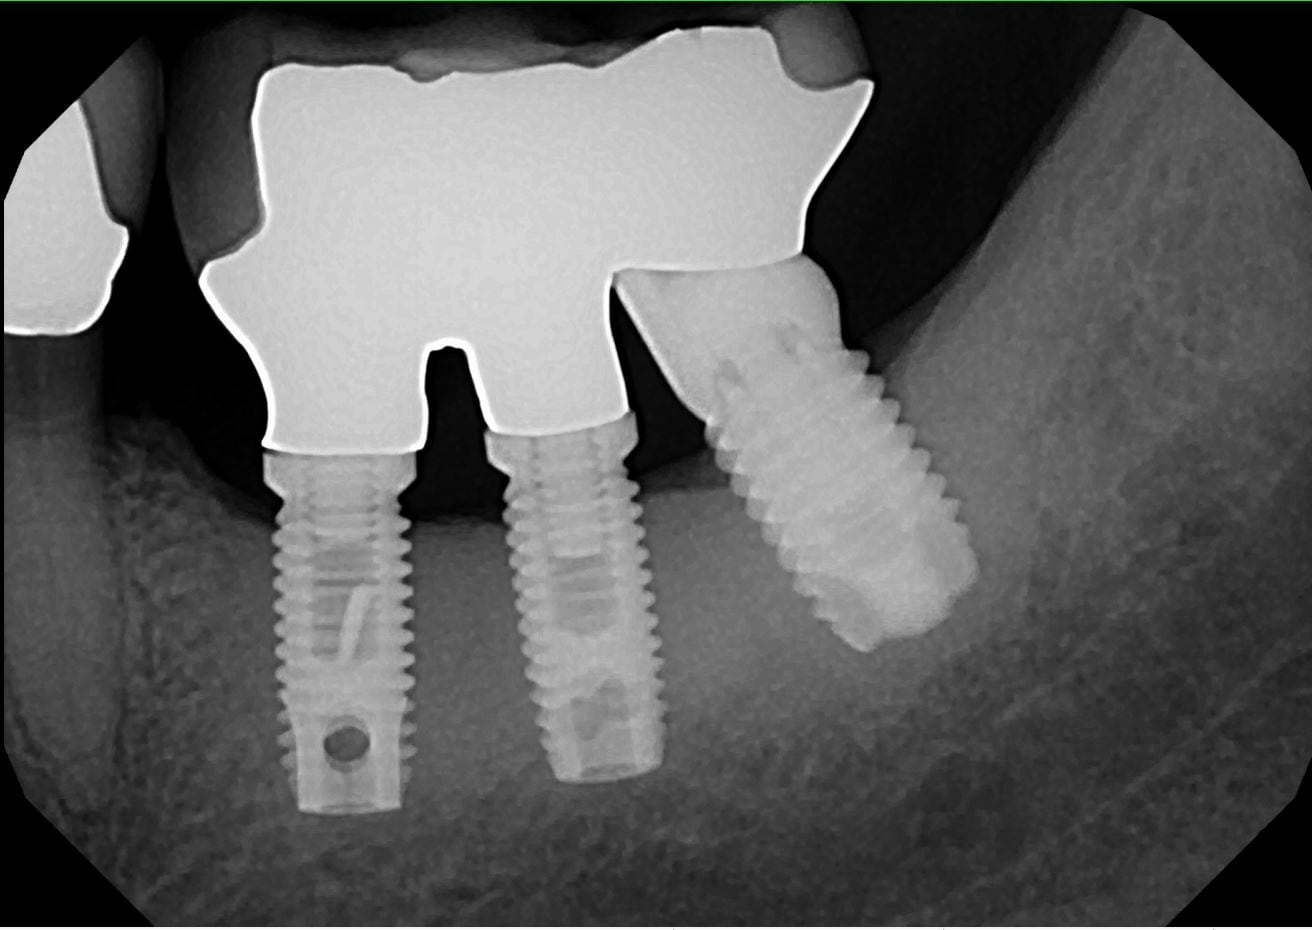

Here's the interesting bit. Years before, he had had two Brånemark implants fitted to replace two front teeth that were lost in military service. In the car park attack, the crowns that had been on the implants were smashed, and one of the metal alloy "anchors" that fits into the implants was bent.

BUT the implants themselves were completely firm and solid! The osseo-integration was so strong and so durable that the dental implants themselves survived the blow.

I could hardly believe it! I made him some temporary crowns and we waited a month for everything to heal up. Then we checked the implants again. Still rock-solid. So then we went ahead and made up new abutments (connectors) and crowns.